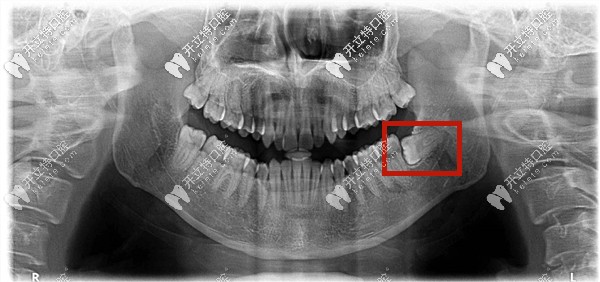

什么是低位阻生齒——就是下頜的阻生智齒的牙冠部位低于前面牙齒的牙頸部以下。

低位水平阻生齒圖片

下頜低位阻生智齒圖片

低位阻生齒——就是牙的高處部位低于第二磨牙的牙頸部,它可以是近中低位,垂直低位,遠(yuǎn)中低位等,也有可能牙全部被包埋在牙骨內(nèi),所以又稱之為骨埋伏阻生智齒。

這種情況下的智齒一般從口中看不到,需要拍片才能確定。